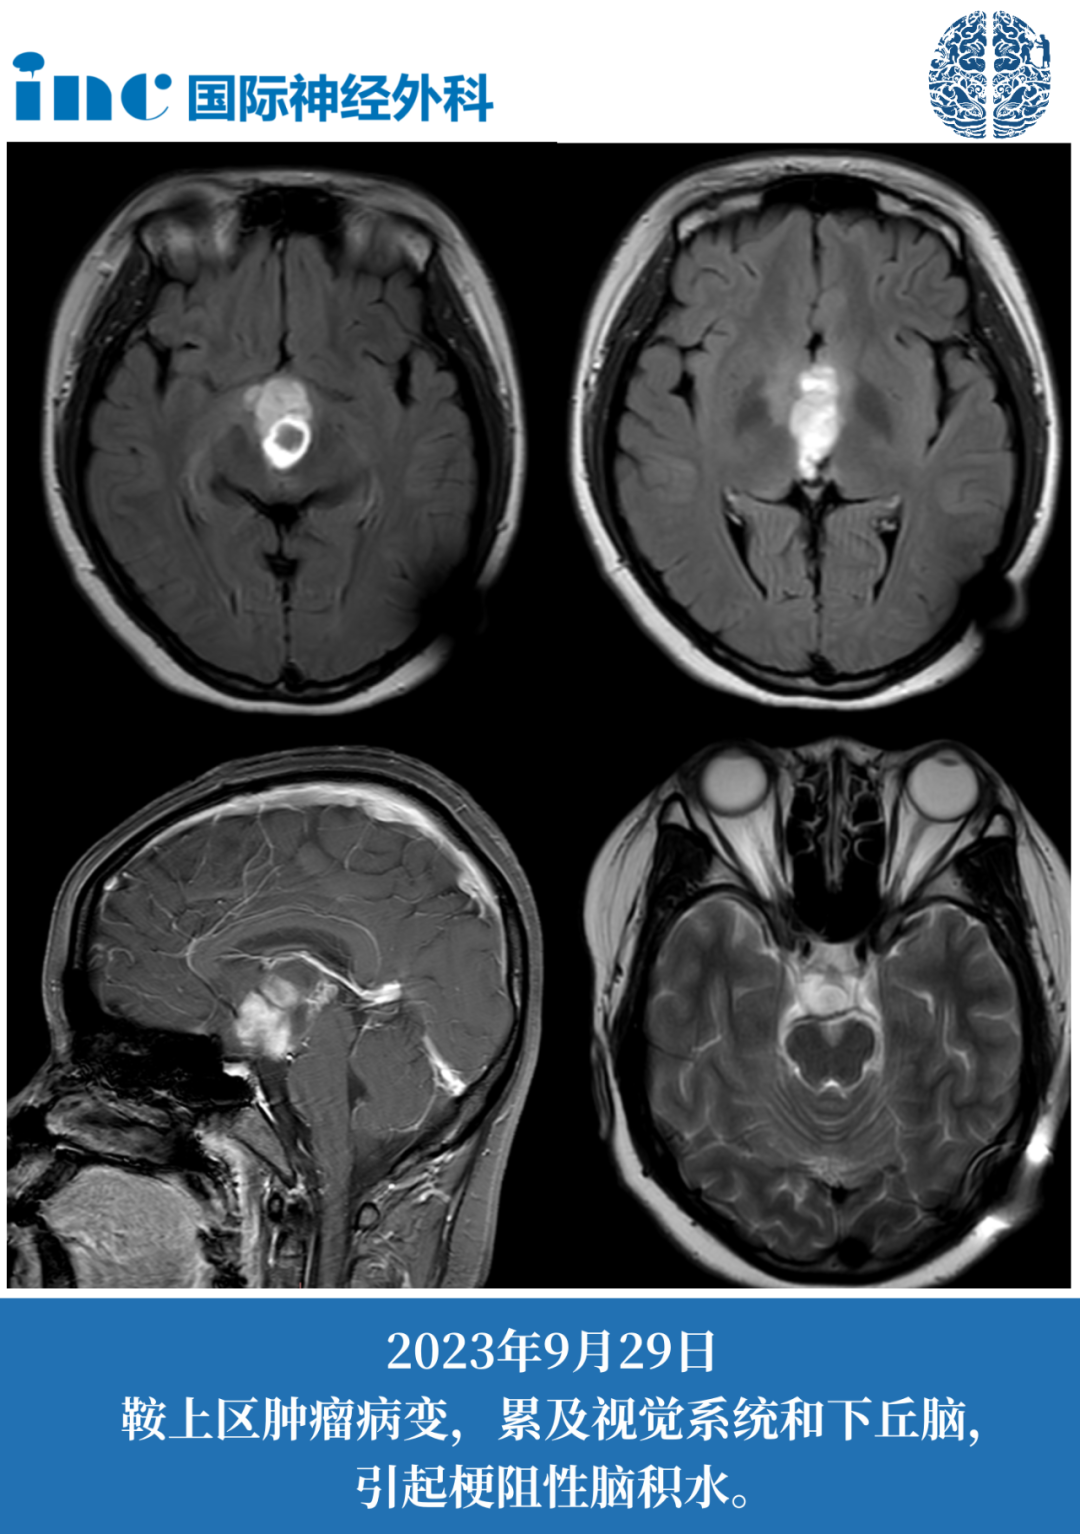

妙妙14歲女孩-鞍區(qū)占位性病變

術(shù)前癥狀:2016年,年僅7歲的女孩妙妙懷疑早熟,父母帶著他去醫(yī)院進一步檢查發(fā)現(xiàn),“罪魁禍?zhǔn)?rdquo;竟是腦子里的腫瘤。雖然腫瘤是可以通過外科手術(shù)切除的,但妙妙的腫瘤位于鞍區(qū),手術(shù)存在風(fēng)險。醫(yī)生建議定期復(fù)查,保守觀察。2023年12月,妙妙癥狀再次加重,復(fù)查發(fā)現(xiàn)腫瘤有很明顯的占位效應(yīng),危及視神經(jīng)及視交叉(兩者已經(jīng)被腫瘤累及),有明確的手術(shù)指征。手術(shù)治療不能再等,腫瘤一旦進一步增大,妙妙可能面臨更嚴(yán)重的問題。

術(shù)后4天普通病房查房:妙妙可以下地行走,狀態(tài)逐漸好轉(zhuǎn),巴教授告知術(shù)后核磁很好,腫瘤已經(jīng)全切。